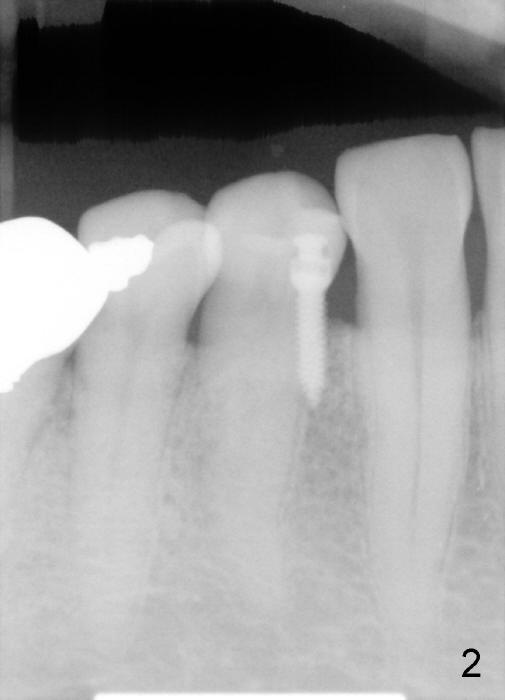

A 1.6x6 mm mini-implant was placed between #27 and 28 on 02/20/2014 (Fig.1,2). The major problem is its angulation. A 1/4 elastic cannot be placed over it. Instead a ligature wire is used to hold the elastic in place (Fig.3,4, taken 2 months later). Occlusal reduction is done (Fig.4), which alleviates the discomfort. But the extrusion is not obvious, since retraction is not 24 hours. The elastic and wire needs replacement quite often, which is not patient friendly. The extraoral Bitewing is taken 2.5 months post implantation (Fig.5). The tooth #6 has a long root. What should we do?